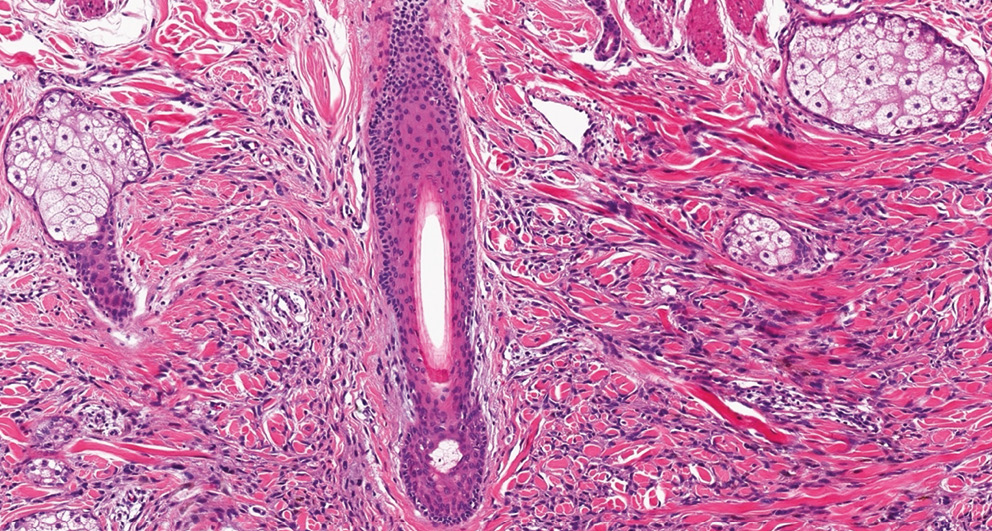

У 40% исследованных пациентов была обнаружена нейротропная инвазия, что усложняло дифференциальную диагностику с опухолями периферической нервной системы [7, 8] (рис. 5). Дополнительные гистологические изменения включали лимфоцитарную инфильтрацию и участки с выраженной десмоплазией, что затрудняло диагностику при окрашивании стандартными гистологическими методами [9, 10].

Рис. 5. Десмопластическая меланома (микроскопическое исследование, × 400, окрашивание гематоксилином и эозином). Периневральная инвазия

Fig. 5. Desmoplastic melanoma (microscopic examination, × 400, H&E staining). Perineural invasion